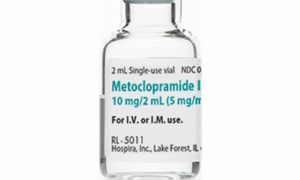

ウマ(馬)の病気  M

M